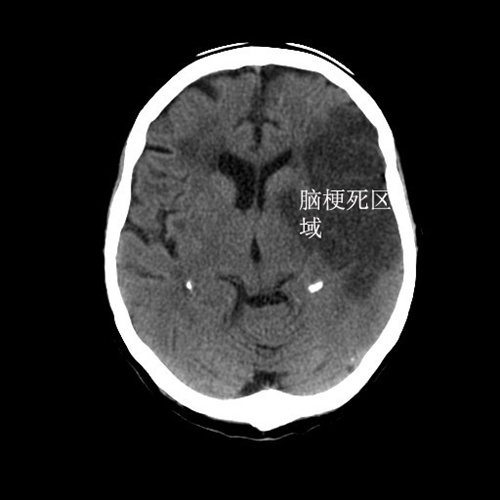

看着这位既往患有20年高血压,现在血压为160/90mmHg的老人,我非常担心会不会是急性脑梗死或者脑出血。不仅是因为老人上一次脑梗塞时也是同样的症状,更加是因为老人已经开始出现右侧肢体肌力下降!

最后检查结果果然提示导致老人出现头痛欲吐的罪魁祸首:脑梗塞!最后这位老人住进了神经内科病房,经过十余天的治疗后康复出院!